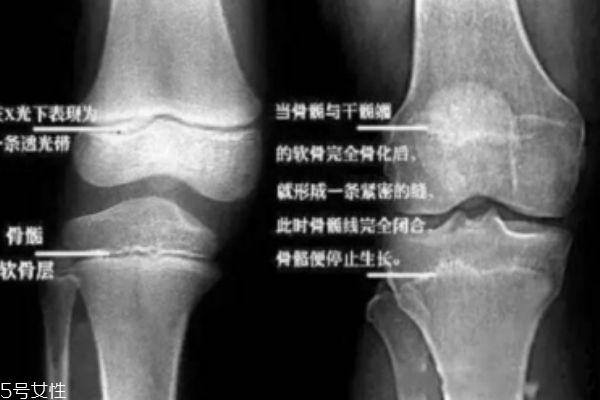

取決于骨骺線(記住它,它是你長高的關(guān)鍵)是否閉合。人體的長高,是全身性的增長,其中最突出的是四肢,尤其是下肢的增長。也就是說,一個人能長到多高,下肢的長骨起了決定性的作用。人在剛出生時,長骨的骨干大部分已經(jīng)骨化,但四肢長骨的兩端還有未骨化的骨骺。骨骺和骨干之間有一層軟骨層,醫(yī)學(xué)上稱之為骺軟骨,即骺板,也叫骨骺線。當(dāng)骺板不斷變薄,最后消失,也就是骨骺與骨干完全閉合時,就完成了骨的發(fā)育。自此,人就不能再長高了……不能再長高了……長高了……我猜你更想問:怎么知道自己的骨骺線閉合了沒呀?很簡單,去醫(yī)院給膝關(guān)節(jié)拍張X光片就一清二楚了。骨骺線還透亮透亮的?恭喜你!你還能再搶救一下!